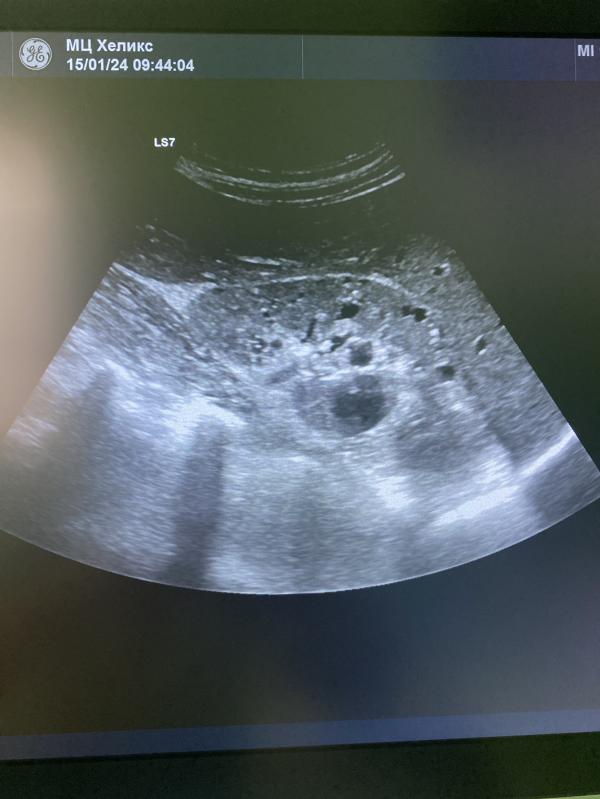

Поликистозные почки.

Случайная находка, ранее девушке узи почек не проводила.

Были жалобы на дискомфорт в области поясницы .